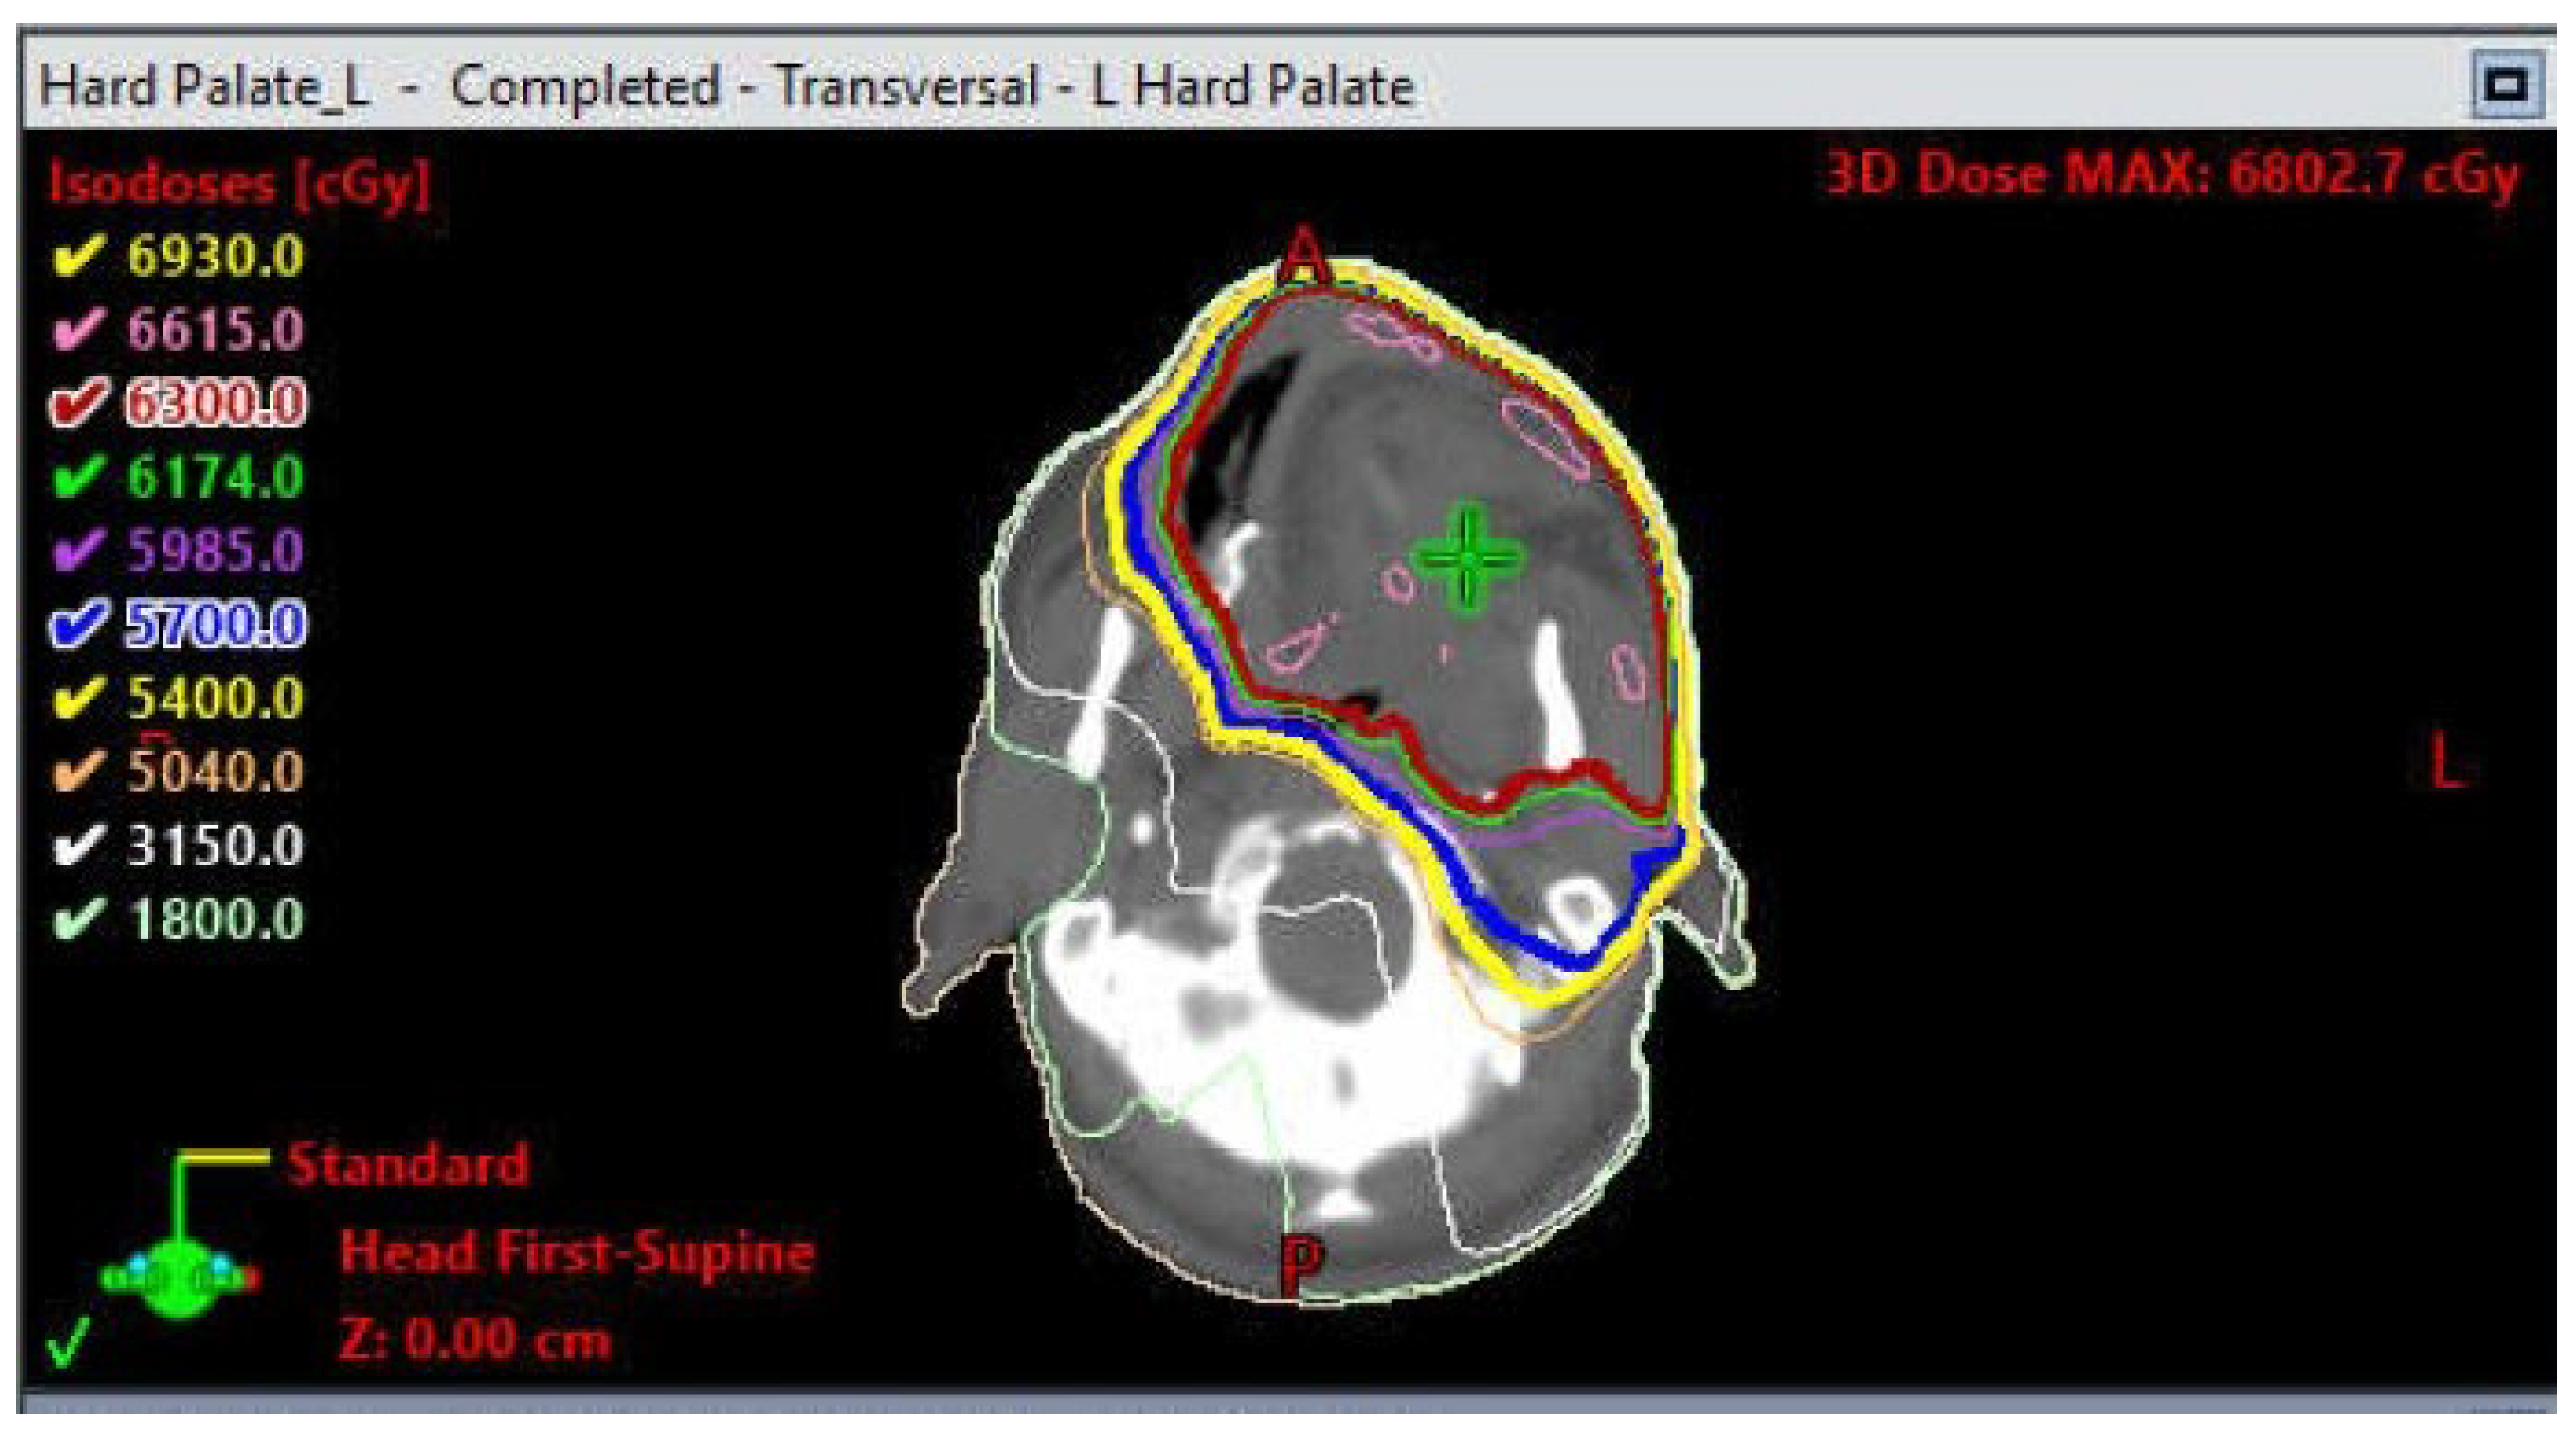

- Romesser, P.B.; Cahlon, O.; Scher, E.; Zhou, Y.; Berry, S.L.; Rybkin, A.; Sine, K.M.; Tang, S.; Sherman, E.J.; Wong, R.; et al. Proton beam radiation therapy results in significantly reduced toxicity compared with intensity-modulated radiation therapy for head and neck tumors that require ipsilateral radiation. Radiother. Oncol. 2016, 118, 286–292. [Google Scholar] [CrossRef] [PubMed]

- Owosho, A.A.; Yom, S.K.; Han, Z.; Sine, K.; Lee, N.Y.; Huryn, J.M.; Estilo, C.L. Comparison of mean radiation dose and dosimetric distribution to tooth-bearing regions of the mandible associated with proton beam radiation therapy and intensity-modulated radiation therapy for ipsilateral head and neck tumor. Oral Surg. Oral Med. Oral Pathol. Oral Radiol. 2016, 122, 566–571. [Google Scholar] [CrossRef]